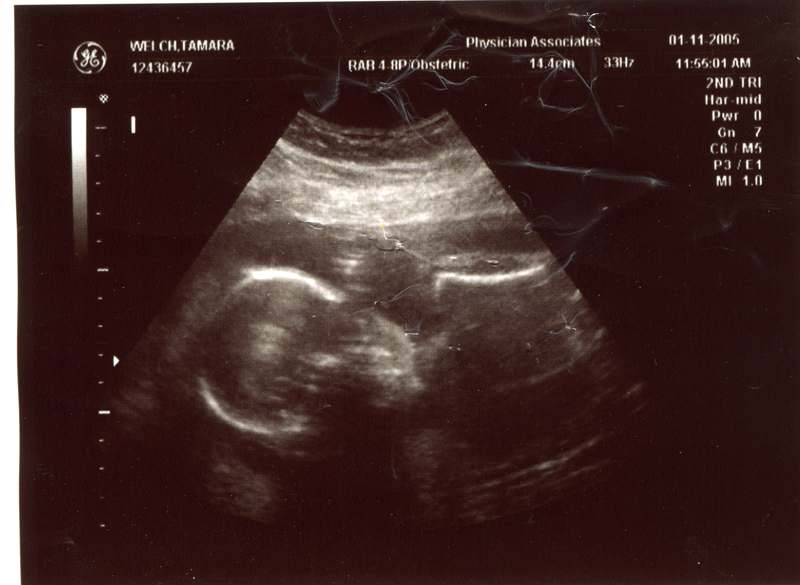

January 11, 2005 - Went to the doctor and had another ultrasound because Tammy hasn't been feeling well. It turns out that the baby is doing fine. The doctor told Tammy to take it easy.